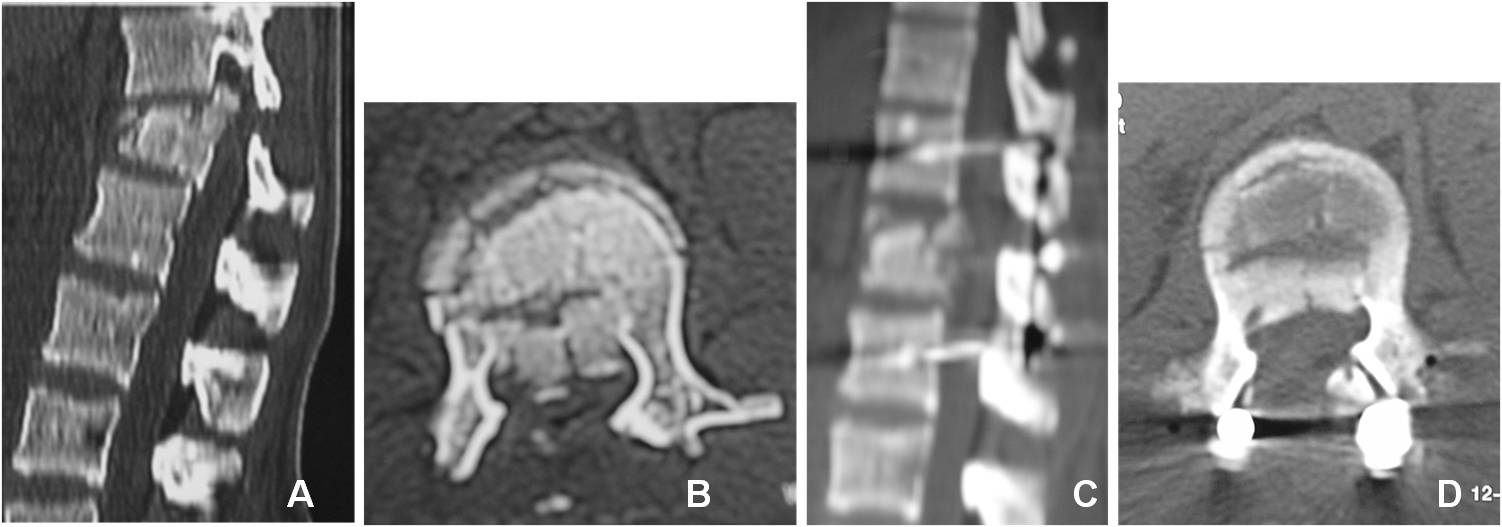

29. Gertzbein SD, Crowe PJ, Fazl M, Schwartz M, Rowed D. Canal clearance in burst fractures using the AO internal fixator.

Spine 1992;17:558-60.

30. Iborra González M, Roca Burniol J, Ubierna Garces MT, Ruíz Calavia JA, Aliaga Orduña F. Remodelación del canal

medular en fracturas toracolumbares. Rev Ortop Traumatol 1997;41:210-2.

31. Day LY. Remodeling of the spinal canal after thoracolumbar burst fractures. Clin Orthop 2001;382:119-23.

32. Vornanen MJ, Bostman OM, Myllynen PJ. Reduction of bone retropulsed into the spinal canal in thoracolumbar vertebral

body compression burst fractures. Spine 1995;20:1699-703.